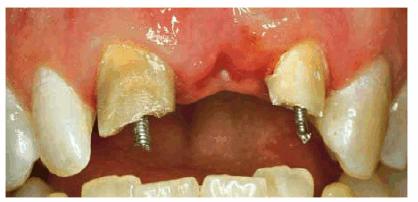

TREATMENT: Because saving teeth was a step-by-step procedure involving

endodontic treatment, periodontal surgery, and reconstructive techniques, the

treatment plan could be changed if one of the suggested treatments failed.

Endodontic therapy had already been completed on both central incisors. These

surgical procedures were performed next: removal of the tooth fragments that

were fractured vertically, labial and lingual gingivectomy and gingivoplasty,

palatal ostectomy, and labial frenectomy (Figur 323s1823d e 18-7C). Approximately 5 mm of palatal

plate was removed to expose new margins on the fractured teeth (Figur 323s1823d e 18-7D). After the tissue healed, gold

posts were constructed and cemented on the two maxillary incisors (Figur 323s1823d es 18-7E to

H). Final

preparations were made, and impressions for aluminous porcelain crowns were

made. The two crowns were seated (Figur 323s1823d es 18-7I

and J Figur 323s1823d e 18-7K is a radiograph of the teeth at the

end of treatment.

Figur 323s1823d e 18-7C and D: Following endodontic therapy and removal of the fractured tooth fragments, periodontal surgery to lengthen the exposed crowns was performed.

Figur 323s1823d e 18-7E to H: Next, two posts and cores were constructed for the endodontically treated teeth.